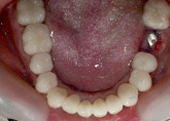

Case from Phuket Dental Crowns & Bridge

teeth crowns bridges

crown bridges

teeth bridges

tooth crown